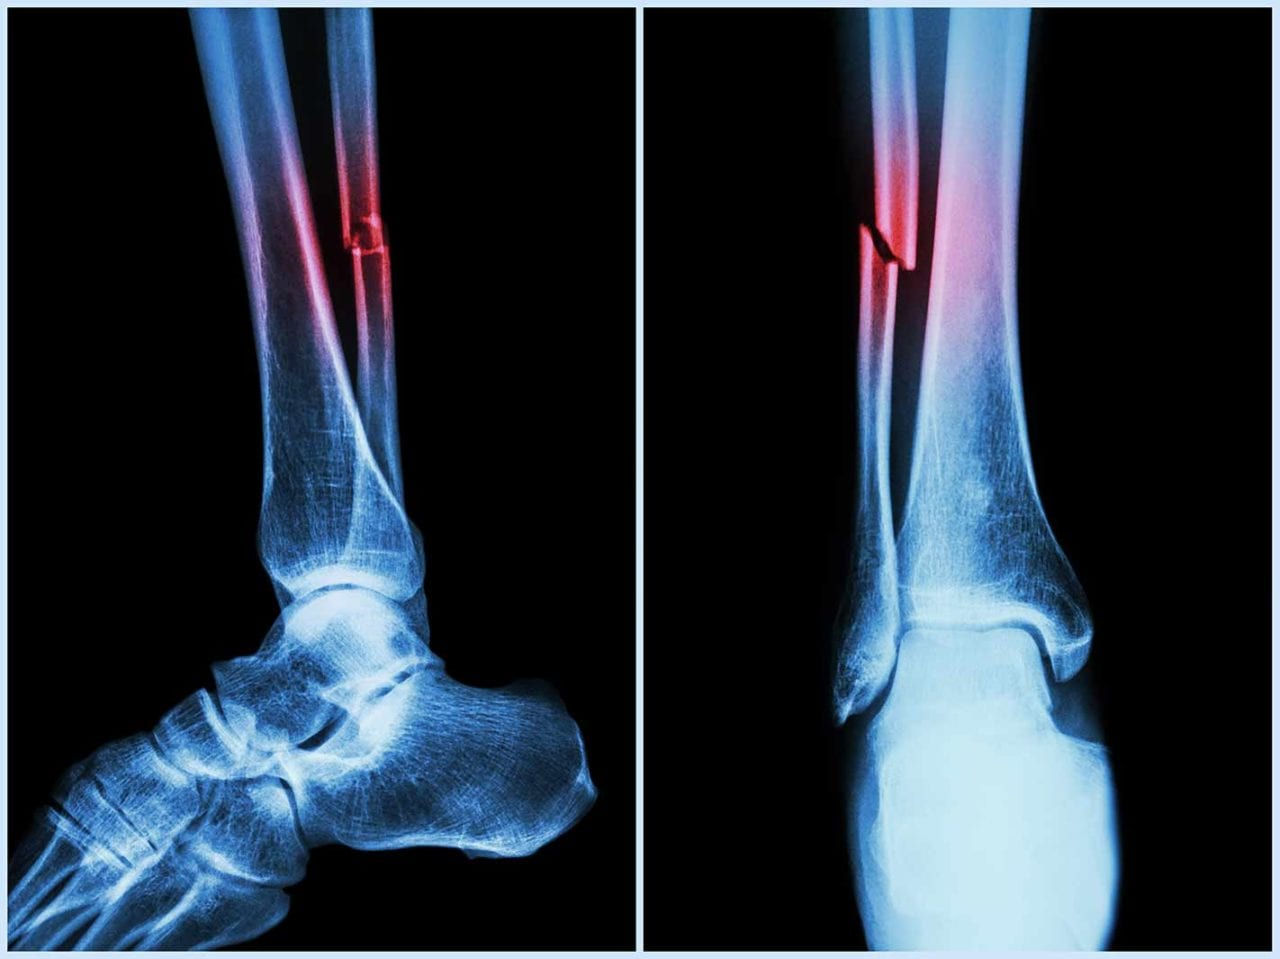

Can AI help patients with bone fractures?

Integrating Artificial Intelligence (AI) with gait analysis can greatly improve treatments for people with fractures, suggests a study today.

Using AI can help predict “post-injury complications such as infection, malunion, or hardware irritation among individuals with lower extremity fractures”, said the researchers in the paper, published in the Journal of Orthopaedic Research.